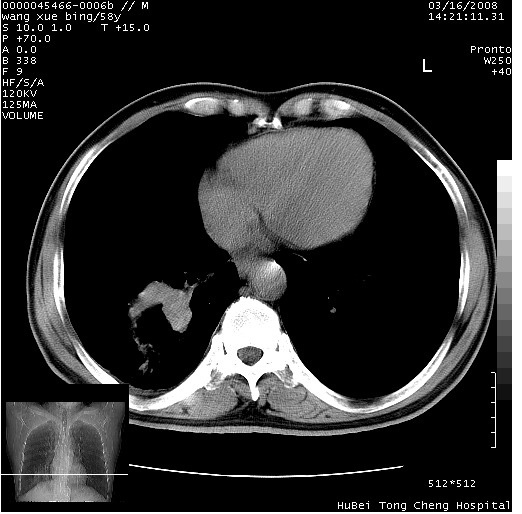

胸部ct轴位平扫(层厚10mm,螺距1.5,重建间隔10mm),图像如下:

考虑右下肺中心型肺癌并远端阻塞性炎症及胸膜及纵隔淋巴转移

支持癌性空洞并远端阻塞性炎症